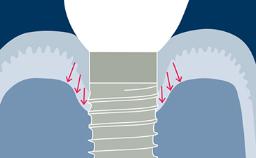

Este módulo concentra-se no conceito de integração de implantes dentários nos tecidos moles e duros da cavidade oral. A integração no osso é chamada de osseointegração e esse fenômeno, em específico, revolucionou essencialmente a maneira como os dentes ausentes podem ser substituídos. A osseointegração tem implicações clínicas para todas especialidades de dentistas envolvidas, bem como para pacientes com qualquer ausência de elementos dentários. Implantes são ancorados no tecido ósseo e penetram no tecido mole. É essencial entender os tecidos moles e duros ao redor de reabilitações sobre implantes dentários, pois somente isso permite reabilitações ideais.

- discutir como ocorre a integração dos tecidos moles e diferenciá-la com a de dentes naturais

- relacionar efeitos de diferentes conexões implante/pilar nos tecidos marginais